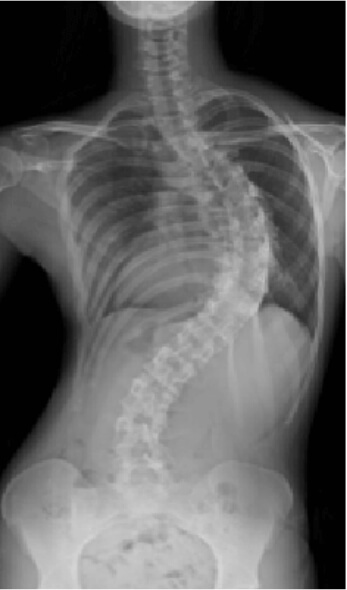

脊柱変形

思春期の女の子に多い特発性側弯症や、成人・高齢者の後側弯症(腰曲がり)などの脊柱変形に対し、椎弓根スクリューを使用した矯正術を行っており、脊椎脊髄病学会認定指導医が厳密な手術適応のもとに、最先端の装置、技術を導入し、安全かつ確実に実施しています。

25歳女性(特発性側弯症:遺残例)

手術前

手術後